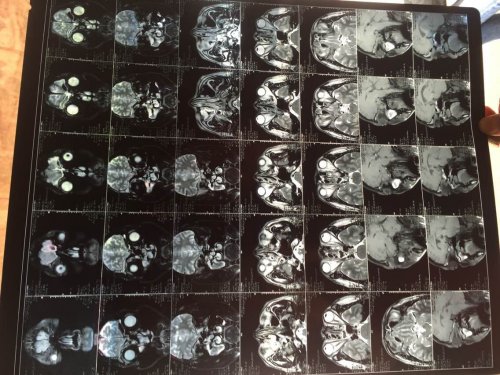

昨日(2015—04—15)MR影像报告:

03—27 影像图:

04—15 影像图

03—27 影像图:

04—15 影像图